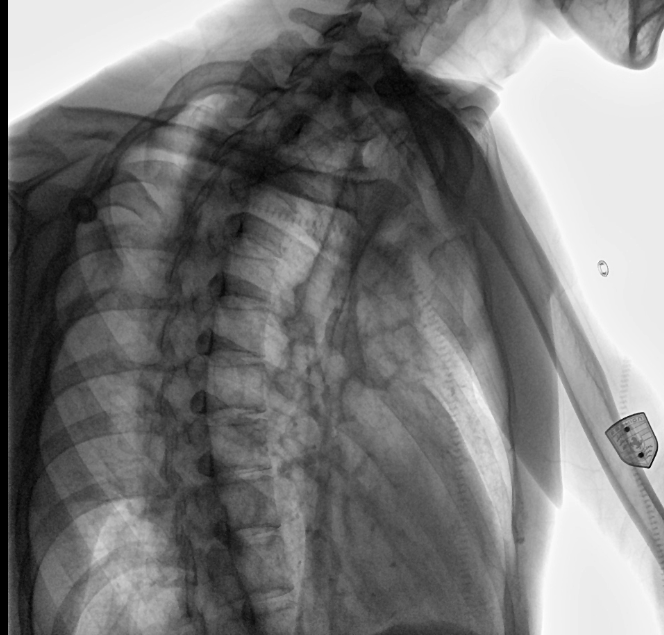

位于衡水市中醫(yī)醫(yī)院的動態(tài)平板數(shù)字化X射線系統(tǒng)DTP571具備高速高清點片功能。這是一款對放射科十分友好的產(chǎn)品。因為它把高速和高清點片結合,既能方便影像技師有效地抓拍需要的病灶的影像,又能給予影像醫(yī)生清晰的影像進行診斷。